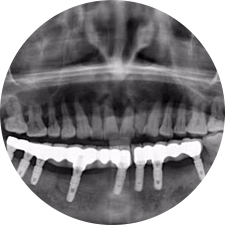

口腔種植是將人工牙根通過手術(shù)植入牙骨內(nèi),獲得牙槽骨牢固的支持,通過特殊的裝置和方式連接牙修復(fù)體,獲得與天然牙功能、結(jié)構(gòu)以及美觀相似的效果。

河北惟德口腔醫(yī)院擁有國內(nèi)豐富的半口/全口、即刻負(fù)重種植案例,十八年案例跟蹤分析,總結(jié)梳理出的各種不同類型的種植案例,Nobel種植體系針對半口/全口缺牙患者,通過4-8顆種植體可快速達(dá)到牙齒重建,不僅植入種植體較少,節(jié)省費(fèi)用,手術(shù)時(shí)間更短。

Noble口腔種植體系基本不受年齡限制,適用于缺牙修復(fù),也適用于牙槽骨萎縮、骨質(zhì)疏松、高血壓、糖尿病、超高齡的患者,即種即用,只需少量微小種植體,便可輕松微痛快速重建全口咬合,特殊力學(xué)設(shè)計(jì),針對許多年紀(jì)較大,骨質(zhì)條件差,身體耐受力差的缺牙老人也能完成“即種即用”,受到廣泛好評。

惟德口腔種植體系是以患者感受為中心,取代傳統(tǒng)種植牙手術(shù)需要翻瓣、打孔、縫合,術(shù)前、術(shù)中、術(shù)后的繁復(fù)流程,采用3D導(dǎo)航微創(chuàng)準(zhǔn)確種植技術(shù),通過數(shù)字化CAD/CAM掃描技術(shù)獲得缺牙患者口腔數(shù)據(jù),以數(shù)據(jù)為基礎(chǔ)重建口腔模型進(jìn)行模擬種植。